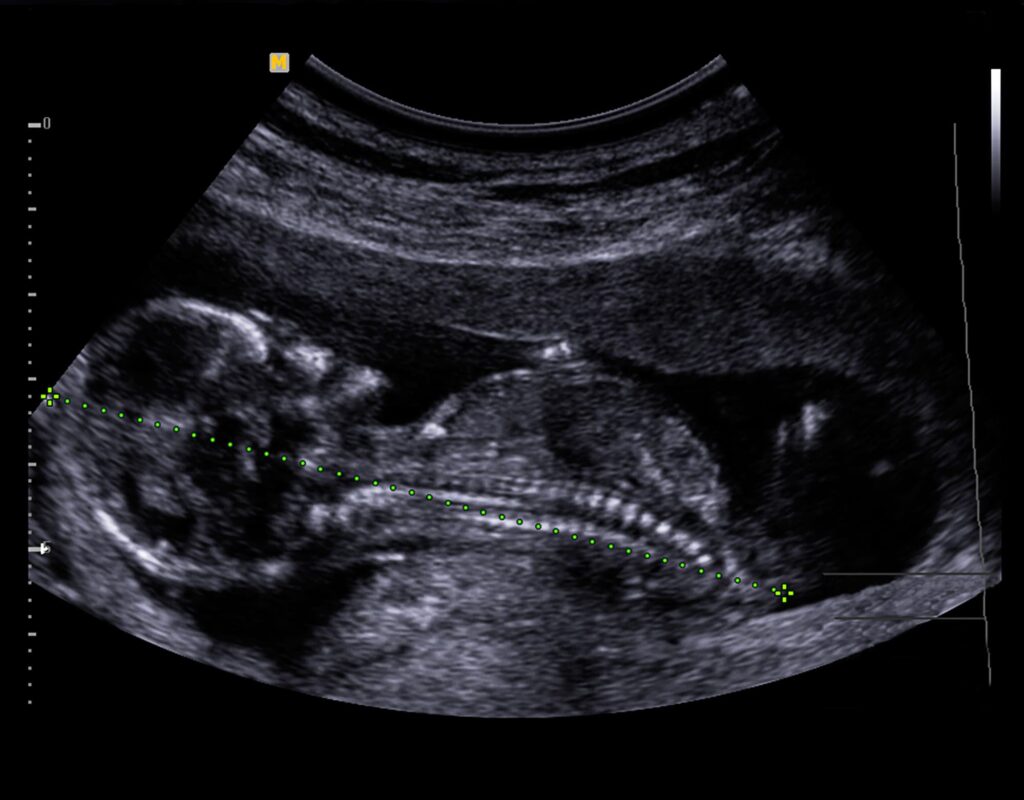

1. 2D- pretecho

Een 2D-echo is een dwarsdoorsnede van je baby, in zwart-wit beeld. De termijnecho en 20-weken echo zijn doorgaans ook in 2D.